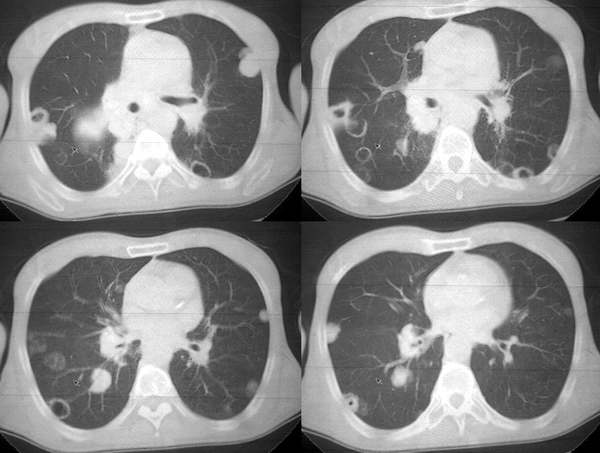

男62肺癌治疗后复查

具体治疗措施不清楚,治疗前空洞很少,请讨论空洞的性质

双肺内及胸壁旁见有多发软组织实性阴影和空洞,实性病变多见有脐凹切迹,贴近胸膜的见有胸膜凹陷征;空洞的壁多为厚薄不均,形态不规则,纵隔内见有较多肿大淋巴结,诊断为双肺内转移性病变。

肺内转移,多发絮壮及环壮.

肺癌双肺内多发空洞转移,原发灶多为腺癌,恶性程度较高.

3.3 cpm的ct特征

cpm灶多为圆形或类圆形、无分叶和毛刺,说明除空洞外cpm 基本保留了转移瘤的形态特点。本组中单个病例出现cpm灶1 16枚,多发与单发者大致相等,说明cpm瘤灶的数目变化大。全部病例的cpm灶均是与肺内多发实性瘤灶共存,而且后者往往远多于前者。另外,当病情好转或恶化时,cpm灶与实性瘤灶同时缩小或增大,说明两者呈同步变化。笔者认为这两点是cpm 最恒定的ct特点。•

单个cpm灶的空洞形态具有多样性,壁可薄可厚,厚度可均匀可不均匀,瘤灶大小变化也大。但总的说来,cpm 的洞壁较薄,4mm以下者最多(53%),其次为4—15mm者(34%),而15mm以上者却较少。另外洞壁厚度均匀者也较多(47%)。笔者认为这些与壁薄而均匀的囊样及小环形空洞较多有关。一般认为壁薄而均匀者多为良性空洞,而癌性空洞的壁多较厚或厚薄不均。woodring等-8 j认为洞壁厚度4mm以下者92%为良性,15mm 以上者95%为恶性,15mm者良恶性各半。蒋瑾等-9 j发现83% 的原发空洞型肺癌的壁厚度超过15mm。以上说明cpm的空洞形态不同于肺良性空洞及原发癌性空洞,具有其独特性。本组40%(16/40)的病例中同时存在多种空洞,说明cpm病例具有空洞类型的混合性。同样的洞腔变化既可见于病情好转时,也可见于病情恶化时,特别是同一种病例可同时出现两种相反的洞腔变化,说明洞腔变化具有非恒定性。